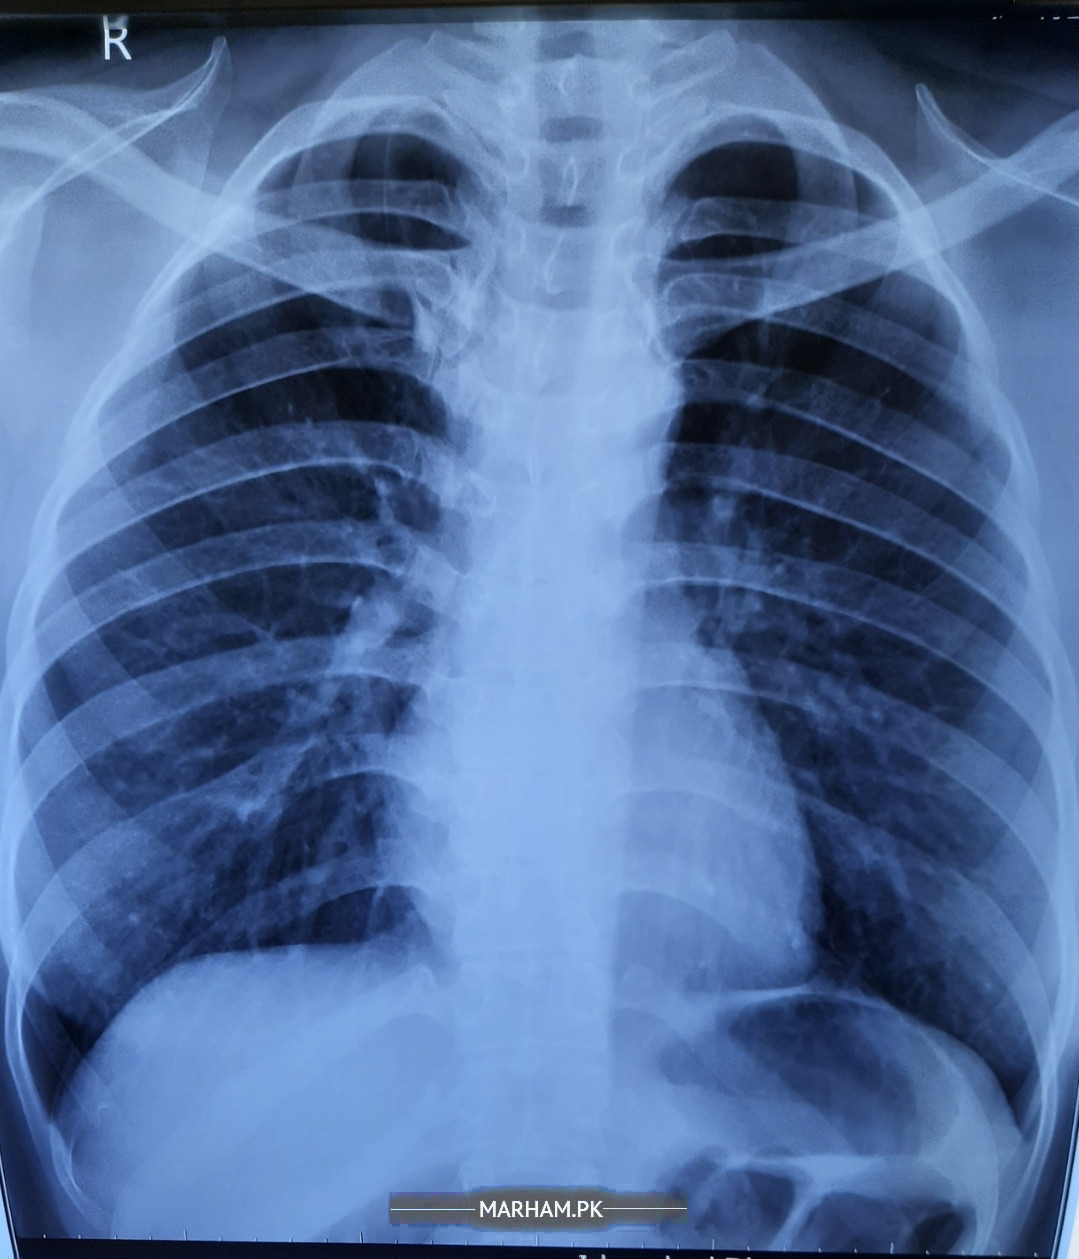

Just done with x Ray (attached). Please some doc can comment on it

X ray